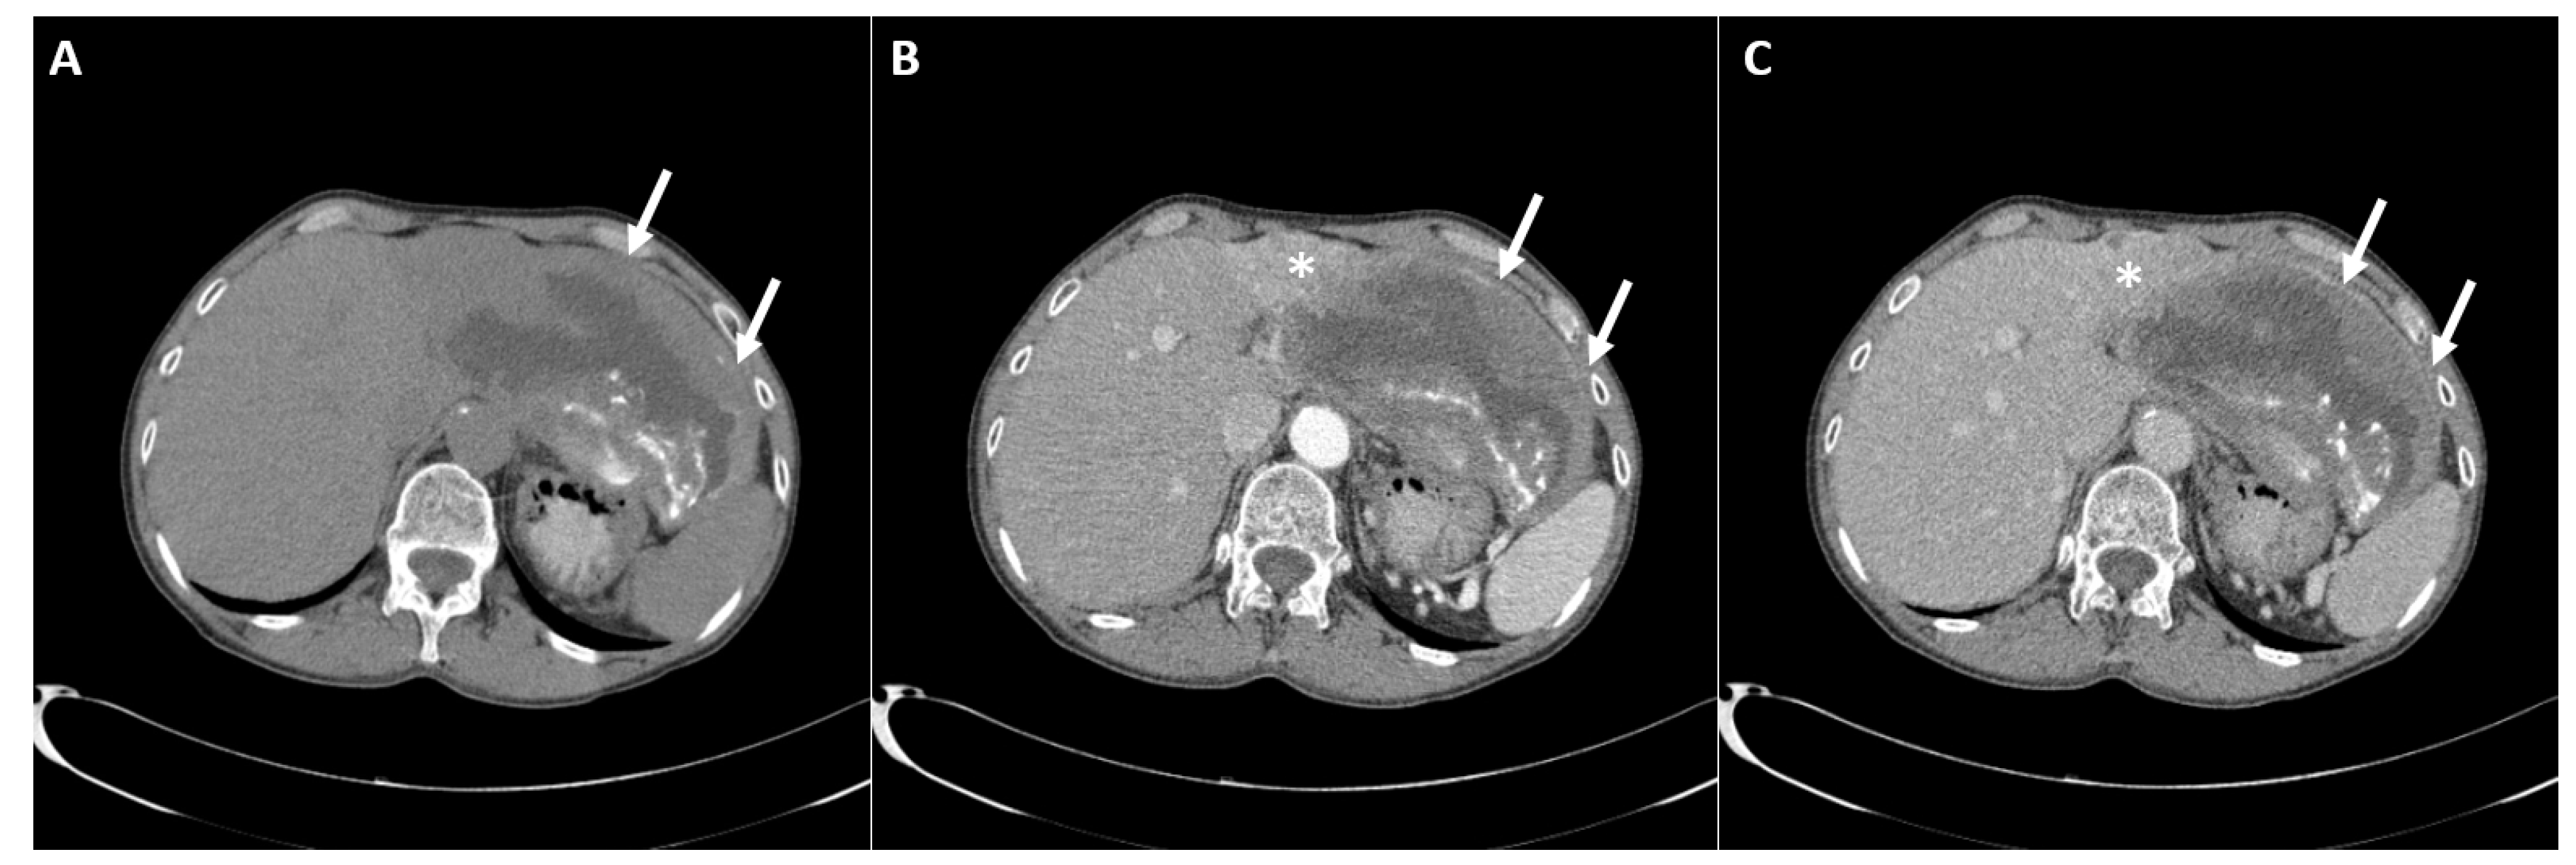

2. Case Report